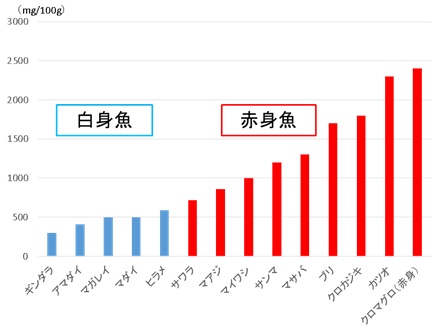

ヒスタミン食中毒は、生魚中で生成された大量のアレルギー反応誘発物質ヒスタミンが原因。ヒスタミンは加熱調理した後でも失活せず、強烈でエピペンが効かないアナフィラキシーを引き起こします(アレルギー様食中毒)。

赤身魚(マグロ、ブリ、サンマ、サバ、イワシ)などのエラや内臓に多く含まれるアミノ酸の一種ヒスチジンが、微生物(ヒスタミン産生菌)の酵素作用でヒスタミンに変化します。赤身魚のエラ・内臓を処理しないまま室温で4-5時間放置すれば、アナフィラキシーを起こすのに十分なヒスタミンが生成されます。ヒスタミンは加熱調理しても分解されません。

また、ヒスタミンはワインやチーズ等の発酵食品にも多く含まれます。

ヒスタミン食中毒の治療は、抗ヒスタミン剤と輸液の対症療法しかありません。

ヒスタミン食中毒の予防は、

- 鮮度が低下した魚を材料にして作られた料理を食べない。例えば、誰かが釣ってきた魚、売れ残った魚で作られた可能性のあるお惣菜。

- ヒスタミンを高濃度に含む食品を口に入れた時、唇や舌先にピリピリした刺激を感じる事があります。決して食べてはなりません。